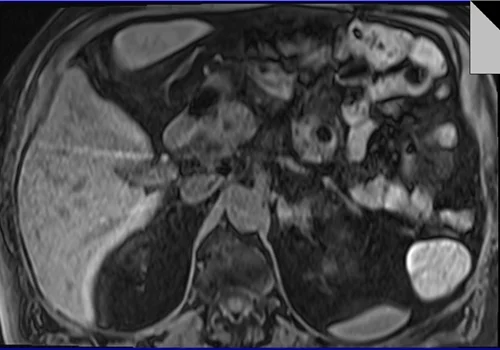

MRI PANCREAS TI VIBE PRE 1 - MRI